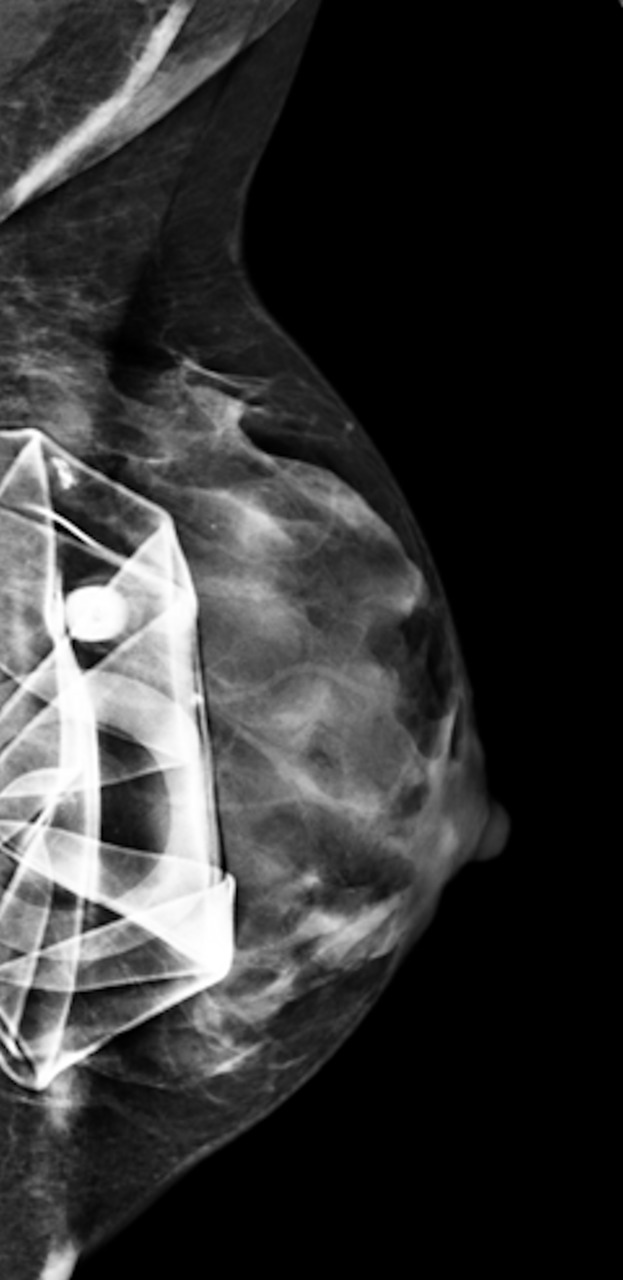

• rupture intracapsulaire : aspect irrégulier de la paroi (linguine sign : images linéaires flottant dans le silicone) en mammo-, échographie ou IRM ;2